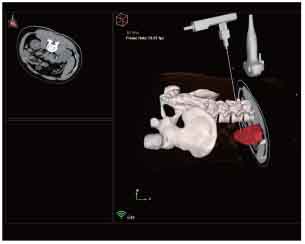

3D navigation and tracking

MRI-Ultrasound Fusion in Transperineal Prostate Biopsy

Bi-planar MRI-Ultrasound real-time fusion

Automatic visualization of lesions and systematic targets